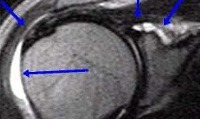

Синовит плечевого сустава. Острое или хроническое воспаление синовиальной оболочки, сопровождающееся образованием экссудата или выпота. Может быть инфекционным или асептическим. Возникает вследствие травм, хронических дегенеративно-дистрофических заболеваний сустава, эндокринных нарушений, аллергических реакций Проявляется припухлостью, болью, ограничением движений и увеличением объема сустава. Диагноз уточняют при помощи рентгенографии, артропневмографии, артроскопии, КТ, МРТ, УЗИ сустава и исследования синовиальной жидкости. Лечение обычно консервативное.

Синовит плечевого сустава - воспалительный процесс в синовиальной (внутренней) оболочке сустава. Сопровождается скоплением излишнего количества жидкости. Является реакцией на внутрисуставное повреждение, раздражение синовиальной оболочки поврежденным фрагментом хряща или кости, недостаточность связочного аппарата, нарушение обменных процессов, действие инфекционного агента или аллергена. Встречается реже других синовитов (например, синовита коленного сустава). Лечение данного заболевания в зависимости от вызвавшей его основной патологии могут осуществлять травматологи, ортопеды, ревматологи, аллергологи и другие специалисты.

Наиболее информативными исследованиями, позволяющими определить причину и характер воспаления, являются лечебно-диагностическая пункция с последующим исследованием пунктата, биопсия синовиальной оболочки, рентгенография, артропневмография, УЗИ плечевого сустава, КТ плечевого сустава и МРТ плечевого сустава. При необходимости применяют артроскопию - лечебно-диагностическую методику, позволяющую оценить изменения в суставе путем прямого визуального осмотра с использованием специального оборудования. При подозрении на аллергические реакции, эндокринные и обменные нарушения назначают консультации аллерголога, эндокринолога и других специалистов.